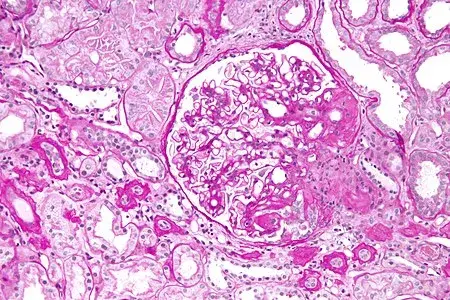

Main Trial: Micofenolato para Nefropatia por IgA

Main Trial: Micofenolato para Nefropatia por IgA

O tratamento da Nefropatia por IgA está longe de ser simples, confere o Trial mais recente que avaliou eficácia do Micofenolato.